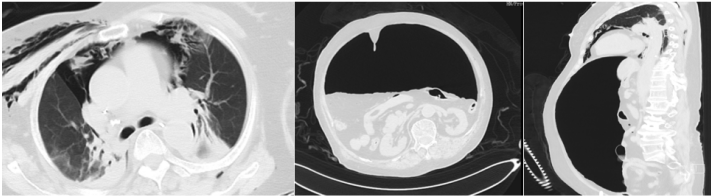

1月12日复查CT:支架位置良好(图13)。予无创通气与高流量交替,拟T管置入。1月14日患者夜间出现刺激性咳嗽,1月15日复查气管镜(软镜)示:声门下腔水肿并坏死物致管腔中度狭窄(图14),冷冻清理坏死物后见硅酮支架下移10 mm,支架第二次移位;声门及声门下腔注入地塞米松5 mg。硅酮支架难题就是肉芽增生和移位,与家属充分沟通后同意T管置入。1月17日全麻硬镜:声门下腔及气管起始部黏膜水肿并坏死物致管腔轻度狭窄,取出硅酮支架,置入T管(图15)。1月19日和20日两次复查气管镜:T管在位,管腔上缘少许坏死物(图16)。病例4:85岁,女性,反复气促2年,外院住院考虑气管外压性狭窄,支架置入失败,心跳骤停,困难插管后3月7日转入我科。入科:气管插管,HR 96次/min,BP 107/86 mmHg,R 24次/min,SpO2 98%(FiO2 100%)。腹膨隆明显。急查胸腹CT示腹腔、纵隔、胸壁及颈部多发积气(图17)。予腹腔穿刺排气。3月11日复查CT示积气明显减少(图18)。3月12日行全院大会诊,考虑结节性甲状腺肿可能,可考虑外科手术。下一步治疗面临难题:继续插管?还是支架置入后手术?与家属充分沟通后,家属拒绝再次支架置入,故继续插管并于3月15日于耳鼻喉科行甲状腺全切术+气管悬吊重建术。术后第3天(3月18日)拔除气管导管,3月28日顺利出院(图19)。因此,并非所有良性气道狭窄都需要介入治疗,解除原发病因最重要。